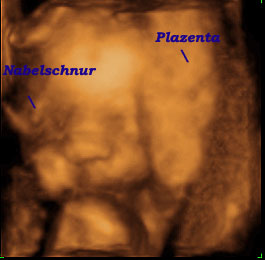

Anschließend konnte Mama das Baby in 4D bewundern.

Leider hat es sich sehr gut hinter der Nabelschnur und der Plazenta versteckt.

Wie ihr seht hat es die Nabelschnur direkt vor der Nase und dem Auge (links).

Rechts versteckt es sich hinter der Plazenta.

Außerdem hält es sich sogar noch mit einer Hand das Ohr zu (Bild rechts).